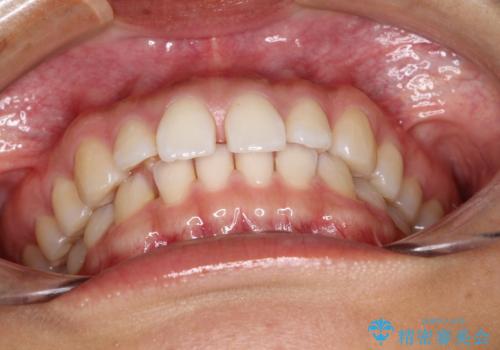

すきっ歯のインビザラインによる目立たない矯正

- すきっ歯を治したいとのことで来院されました。

上下ともに前歯に隙間がありました。

目立たない装置をご希望のためインビザラインで矯正治療を行うこととしました。

使用時間を守っていただけたので、スムーズに治療を終わることができました。